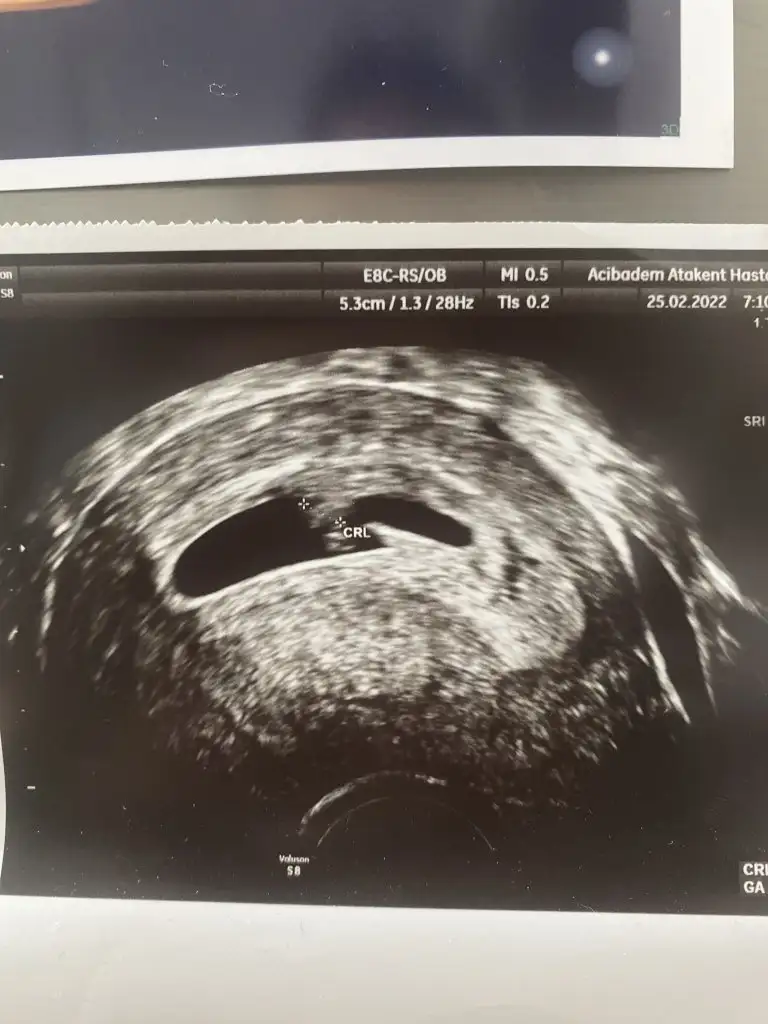

Yok canım bilmediğimden soruyorum öyle görmek istediğimden değil. Bak birlikte oldukları fotoda üstteki sol olmuyor mu? Çok anladığım işler değil neye göre sağ/sol bilmiyorum zatenİlk fotoyu attığımda tek kese vardı ve erkek demiştin. Bugün gittim bi de ne göreyim çift keseVajinal ultrason biri 7+1 diğeri 6+6. Üstte sonradan beliren kesedeki bebiş solda gibi

8+3 vajinal ultrasonSelam Kızlarbir çok kişi gruplardan beni bilir. Yine yetiştim imdatlara